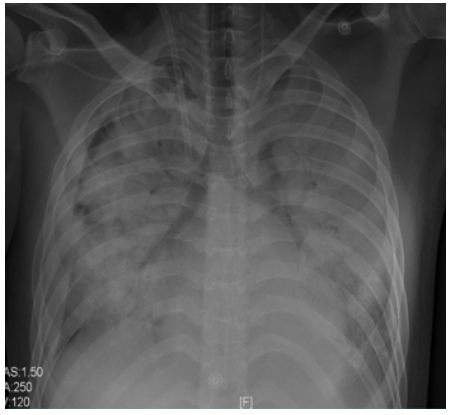

胸片:两肺感染,肺水增多(图11)

图片

图11  患者入院后胸片